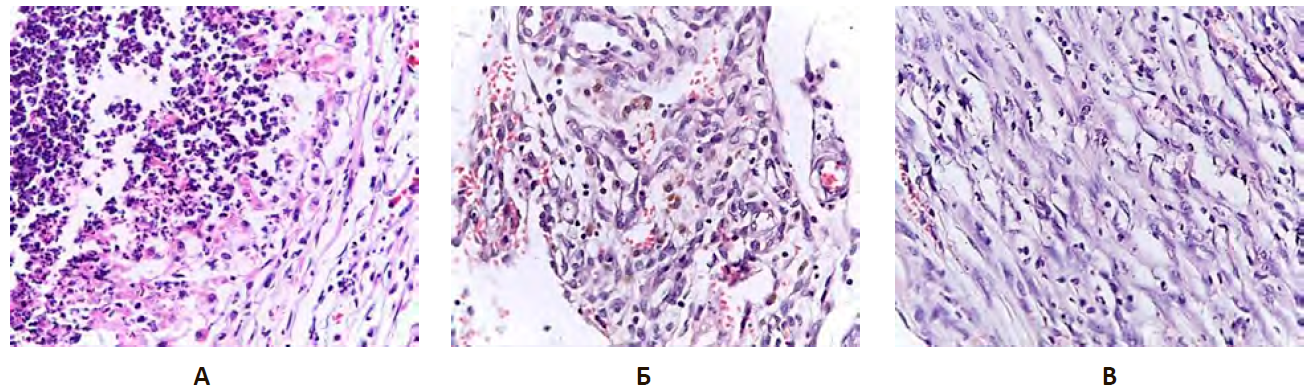

На 10-е сутки эксперимента в группе НКэп в плевральной полости определялось пропитывание листков плевры гнойно-фибринозным экссудатом с вовлечением в патологический процесс прилежащих тканей. В воспалительном детрите экссудата определялись отложения нитей фибрина. В париетальной плевре обнаруживались реактивные изменения, характеризующиеся явлениями гиперхромии ядер и нарушениями ядерно-цитоплазматического взаимоотношения. Воспалительный инфильтрат был представлен обилием полиморфно-ядерных нейтрофилов с единичными лимфоцитами и макрофагами (рис. 11А).

В группе сравнения в остаточной полости ЭП также обнаруживался гнойно-фибринозный экссудат. Выявлены признаки воспаления, заключающиеся в визуализации клеток мезотелия с воспалительными измениями. В плевральных сращениях определялись хаотично расположенные соединительнотканные волокна, преимущественно ретикулярные, в толще которых располагались единичные фибробласты и множественные нейтрофильные лейкоциты (рис. 11Б).

В опытной группе остаточная плевральная полость была отграничена от ткани легкого за счет формирования грануляционной ткани, представленной волокнами соединительной ткани с обилием сосудов (рис. 11В).

Рисунок 11 – Формирование незрелой соединительной ткани при эмпиеме плевры на 10-е сутки эксперимента на фоне хронической эмпиемы плевры крыс

Примечание: А. Группа негативного контроля (НКэп). Б. Группа сравнения (ГСэп). В. Опытная группа (PRPэп) при введении плазмы, обогащенной тромбоцитами. Окраска гематоксилином и эозином. Ув. ×400.

В группе НКэп на 20-е сутки экспериментальной ЭП выявлена частичная организация экссудата с осадком фибрина и единичных волокон соединительной ткани. Обнаруживались немногочисленные микроабсцессы с тканевым дендритом, расположенном в центре. Отграничение патологического процесса происходило посредством незрелых волокон соединительной ткани, внутри которых отмечалась массивная воспалительная инфильтрация, представленная нейтрофилами с единичными лимфоцитами и макрофагами. Отмечалось несоответствие степени зрелости плевральных сращений срокам эксперимента (рис. 12А).

При введении доксициклина на 20-е сутки эксперимента адгезиогенез имел ряд особенностей, связанных с фрагментацией остаточной полости соединительнотканными сращениями на микрополости, содержащие незначительное количество серозно-гнойного экссудата. Обнаруживаемые спайки были инфильтрированы нейтрофильными лейкоцитами и богато васкуляризованы, что свидетельствовало об активном неоангиогенезе (рис. 12Б).

Введение плазмы, обогащенной тромбоцитами, на данном сроке эксперимента приводило к активному формированию соединительной ткани, представленной сетью рыхло расположенных тонких волокон с явлениями отека. При этом выраженность воспалительной реакции была значительно ниже, чем в группе НКэп и ГСэп. Морфологически определялась умеренная диффузная лимфоцитарная инфильтрация плевральных сращений с единичными нейтрофильными лейкоцитами. Со стороны микроциркуляторного русла были выявлены признаки активного неоангиогенеза, сосуды равномерно располагались среди волокон соединительной ткани (рис. 12В).

Рисунок 12 – Экспериментальная эмпиема плевры на 20-е сутки эксперимента

Примечание: А. Группа НКэп. Окраска гематоксилином и эозином. Ув. ×100. Б. Группа сравнения. Окраска гематоксилином и эозином. Ув.х100. В. Опытная группа (PRPэп) при введении плазмы, обогащенной тромбоцитами. Фаза молодых сращений с наличием незрелой соединительной ткани на фоне хронической эмпиемы плевры крыс на 20 сут при введении плазмы, обогащенной тромбоцитами. Окраска гематоксилином и эозином. Ув. ×100.

При гистологическом исследовании тканей плевральной полости на 30-е сутки в группе негативного контроля наблюдался выраженный отек соединительной ткани, обильно инфильтрированной нейтрофилами, единичными плазмоцитами и макрофагами. Мезотелий висцерального и париетального листков не визуализировался, между тонкими тяжами соединительной ткани определялся экссудат, который по своему составу был представлен преимущественно нейтрофилами. Выявлено диффузное пропитывание и утолщение плевральных листков за счет выраженного отека и обильной нейтрофильной инфильтрации. Сосуды микроциркуляторного русла были умеренного кровенаполнения, с явлениями периваскулярного отека, что гистологически проявлялось разволокнением сосудистой стенки и наличием оптически пустых периваскулярных пространств (рис. 13А).

У животных группы сравнения (на фоне введения доксициклина) отмечалось наличие единичных незрелых спаек в плевральной полости. Спайки были сформированы рыхлой волокнистой соединительной ткани, при этом тонкие соединительнотканные волокна имели различное направление, между которыми выявлялось обилие умеренно полнокровных сосудов. Между волокнами соединительной ткани четко визуализировалось скопление фибробластов, которые имели округлые ядра и незначительное количество цитоплазмы. Кроме этого определялась лимфоцитарная инфильтрация с наличием единичных плазматических клеток. В плевральных сращениях определялись гранулы гемосидерина, а также крупные клетки с наличием в цитоплазме бурого пигмента (сидерофаги). Обращало на себя внимание, что сосуды микроциркуляторного русла были выстланы эндотелиоцитами с округлым ядром, что свидетельствовало о «раздражении» эндотелия и являлось морфологическим признаком эндотелиальной дисфункции (рис. 13Б).

В опытной группе с биологическим потенцированием адгезиогенеза в плевральной полости плазмой, обогащенной тромбоцитами зарегистрировано образование множественных спаек с наличием строго ориентированных соединительно-тканных волокон, где определялись фибробласты и фиброциты с вытянутым ядром и незначительным количеством цитоплазмы. Визуализировались единичные сосуды с эндотелием типичного строения. Морфологические признаки воспаления были минимальны и характеризовались наличием единичных лимфоцитов и плазматических клеток (рис. 13В).

Рисунок 13 – Экспериментальная эмпиема плевры на 30-е сутки эксперимента

Примечание: А. Группа НКэп. Б. Группа сравнения. В. Опытная группа (PRPэп) при введении плазмы, обогащенной тромбоцитами. Зрелая спайка в плевральной полости крыс с наличием ориентированных соединительно-тканных волокон, незначительным количеством лимфоцитов на фоне хронической эмпиемы плевры. Окраска гематоксилином и эозином. Ув. ×400.